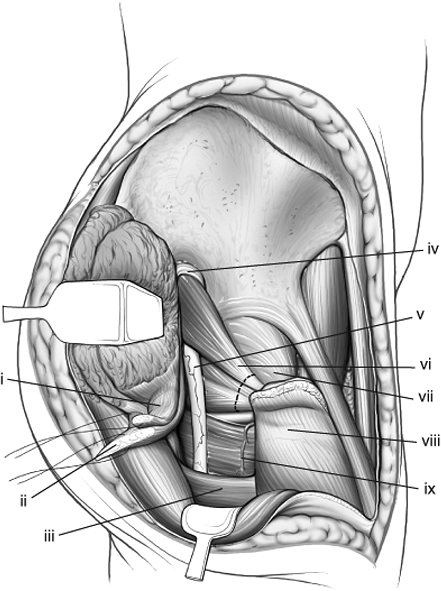

![]() |

|

Figure 43.4. Access to the right pelvis via the extended iliofemoral approach. A. Lateral (outer) bony pelvis. B. Medial (inner) bony pelvis.

Figure 43.5. Maximal exposure of right acetabulum via the extended iliofemoral approach. (i) Gluteus medius muscle. (ii) Gluteus minimus muscle. (iii) Blunt Homan in lesser sciatic notch. (iv) Greater trochanter. (v) Tensor fascia-lata muscle. (vi) Malleable retractor under the iliacus muscle. (vii) Superior–gluteal neurovascular bundle. (viii) Piriformis muscle. (ix) Sciatic nerve. (x) Pointed Homan retractor over the anterior capsule of the hip. (xi) Hip-joint capsule.

elevation of all the gluteal muscles with the tensor fascia lata, (b)

division of the external rotators of the hip, and (c) an extended

capsulotomy along the lip of the acetabulum. The end result is complete

exposure of the outer aspect of the ilium and the whole posterior

column inferiorly to the upper part of the ischial tuberosity.

Furthermore, the approach may be extended to allow a limited exposure

of the internal iliac fossa and the anterior column to the level of the

iliopectineal eminence. This allows simultaneous exposure of both

columns and permits direct visualization of the reduction and fixation

of the anterior and posterior columns (see Fig. 43.4).

further access to the internal iliac fossa and acetabulum is possible.

This access is obtained by subperiosteal dissection beneath the

sartorius and direct head of the rectus or by osteotomy of the superior

and inferior iliac spines, which will, respectively, release these

muscles (see Figs. 43.5 and 43.13).